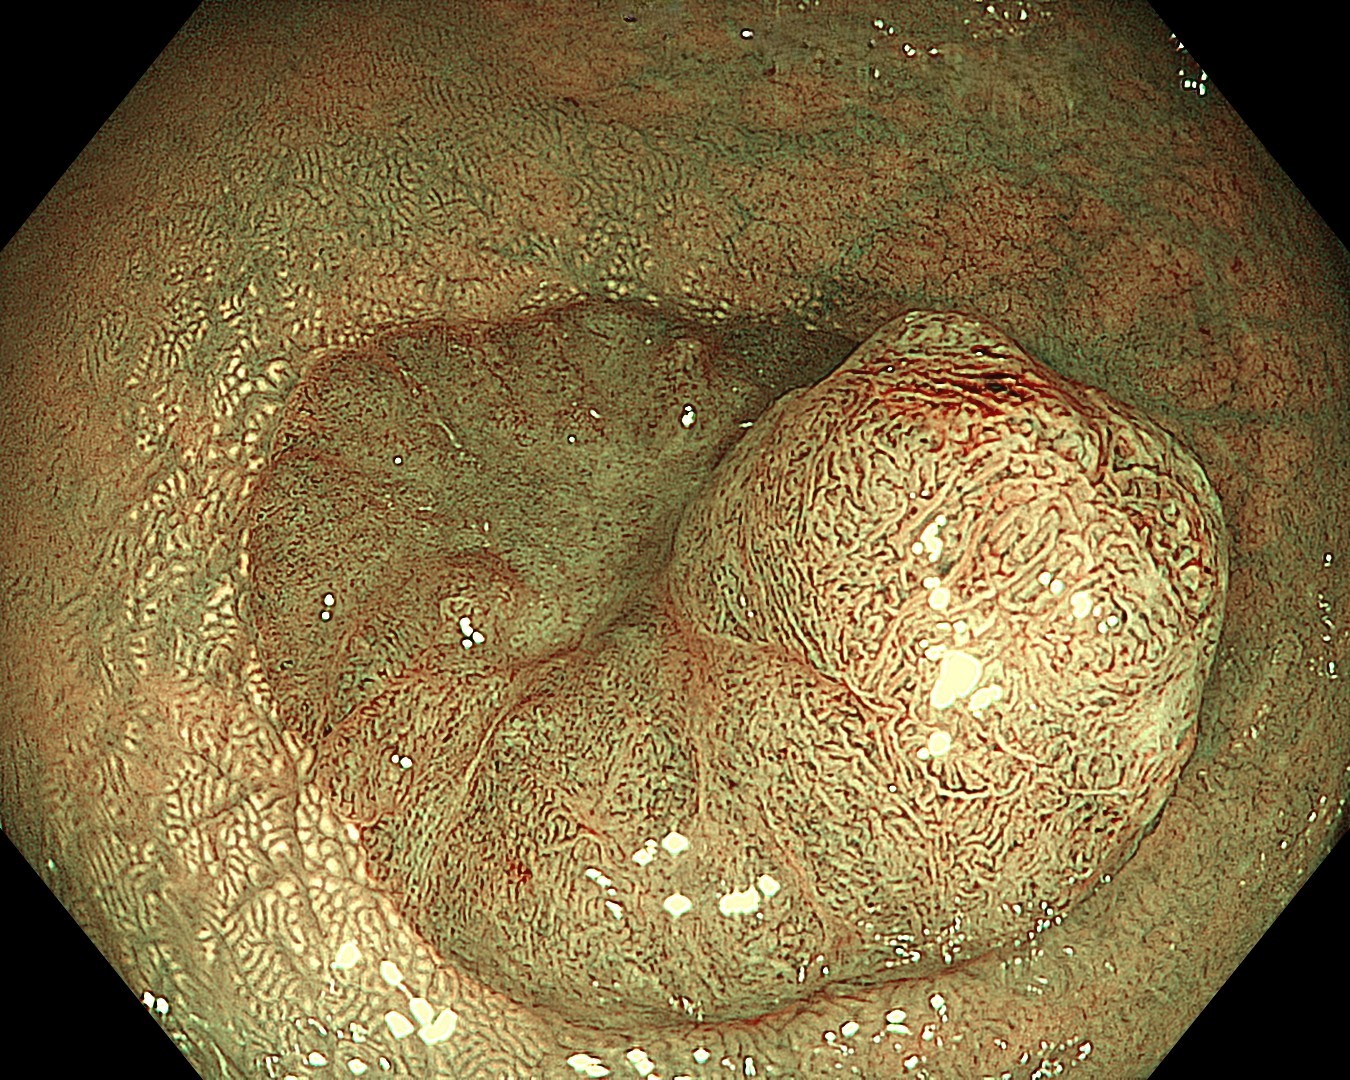

• NBI+TXI観察②(近景)

切替前:NBI強調設定:B8

NBI+TXIレベル:高

図7

平坦隆起部でも、NBI+TXI観察では、血管密度の上昇や分岐異常を伴う領域がより容易に捉えられた。